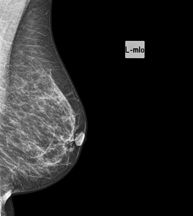

Mamografia

Els estudis de Mamografia obtenen imatges generades a partir de raigs X de dosi molt baixa que permeten detectar les diverses patologies dels teixits mamaris (en especial el càncer de mama), tant per al cribratge (screening) ginecològic com per al diagnòstic dirigit. La mamografia pot ser intervencionista amb punció de quists, biòpsia estereotàxica, marcatge prequirúrgic i galactografia.

Mamografia digitalitzada

La mamografia digitalitzada és una tècnica innovadora que permet estudiar la mama amb un dosi baixa de radiació, que és més reduïda que la mamografia convencional. La imatge es digitalitza a partir d'uns bastidors especials, anomenats CR. Gràcies a aquestes tècniques de digitalització s'obtenen imatges excel·lents, sobretot en mames de difícil estudi com les glàndules que es presenten en la mamografia com una mama densa, i permet detectar millor en aquest grup de pacients les tumoracions.